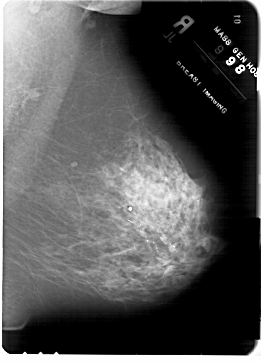

A_1817_1.LEFT_MLO

LEFT_MLO LINES 6871 PIXELS_PER_LINE 4831 BITS_PER_PIXEL 12 RESOLUTION 43.5 OVERLAY